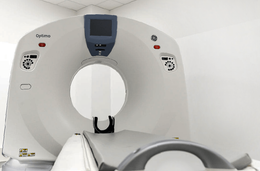

- Tomografia Computerizzata (TC) Multislice